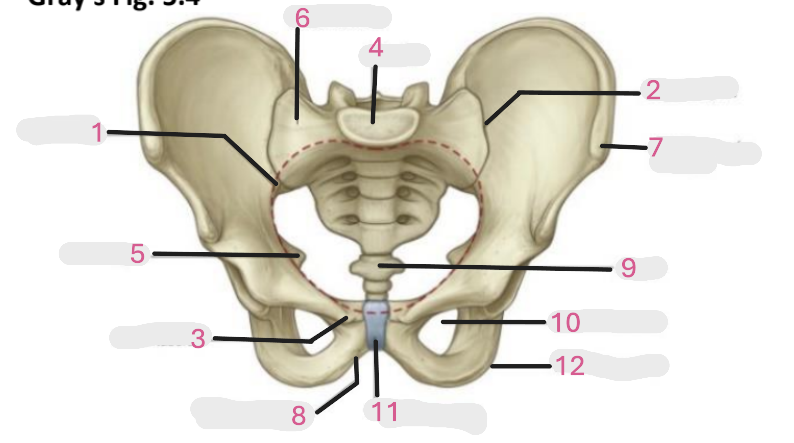

Where is the pelvic inlet

1

Where is the sacro-iliac joint

2

Where is the pubic tubercle

3

Where are the S1 body

4

Where is the ischial spine

5

Where is the ala of sacrum

6

Where is the anterior superior iliac spine

7

Where is the ischiopubic ramus

8

Where is the coccyx

9

Where is the obturator foramen

10

Where is the pubic symphysis

11

Where is the ischial tuberosity

12